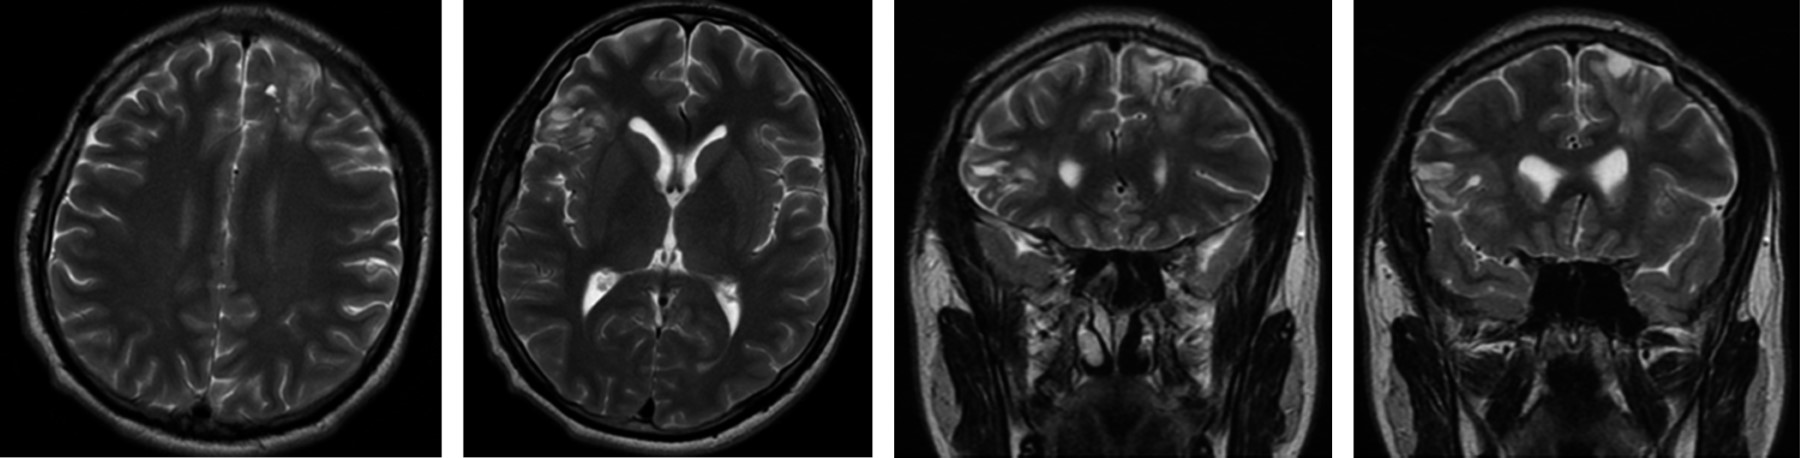

Absceso cerebral bilateral frontal, medicina hiperbárica, cirugía y terapia antimicrobiana en germen extraño. Reporte de caso y revisión de la literatura

El absceso cerebral es un evento extraño en el paciente inmunológicamente competente, por lo general secundario a procesos infecciosos en cavidades craneales, principalmente en senos paranasales, celdillas mastoideas y oído medio. Diferentes esquemas de manejo han sido propuestos en presencia de microorganismos que día a día son más resistentes a los tratamientos farmacológicos. Dependiendo del tamaño y la localización, los abscesos cerebrales requieren tratamiento médico y quirúrgico en conjunto con técnicas modernas como la terapia hiperbárica. Presentamos un caso clínico de un hombre de 20 años con cefalea intensa y compromiso del estado neurológico secundario a dos abscesos en lóbulos frontales con erradicación del 100% de las colecciones y mejoría del estado neurológico y funcional del paciente.

Figura 2

Figura 3